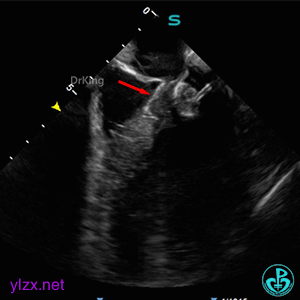

锁定封堵器后观察位置形态

锁定后可见位置形态完好,盘面平整,扣合良好,无周围瓣膜影响。